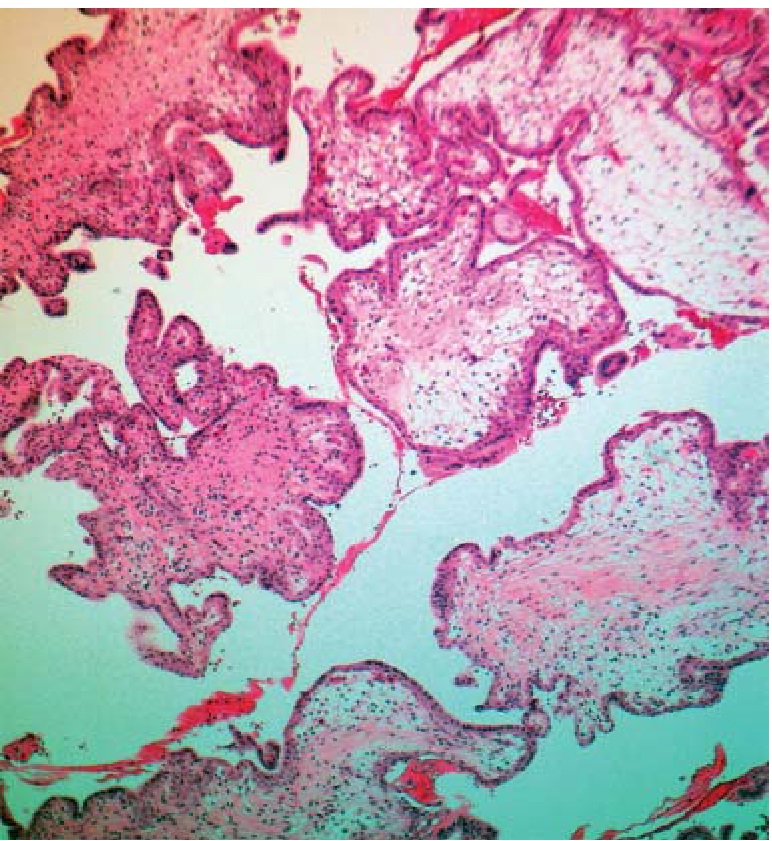

В группе с трисомиями по 21-й и 22-й хромосомам наблюдались единичные васкуляризированные ворсины. Строма отличалась умеренной целлюлярностью. Гидропическая дистрофия имела очаговый характер, без кистозной трансформации ворсин. Характерной особенностью было обнаружение центрально развивающегося фиброза и гипоплазии более чем в 1/3 ворсин во всей группе (рис. 1). Хориальный эпителий имел двухслойную выстилку с умеренной и выраженной атрофией. Исследования G. Pidoux et al. [10] позволили выдвинуть гипотезу о том, что при трисомии по 21-й хромосоме слабая биоактивность хорионического гонадотропина и низкая экспрессия рецепторов лютеинизирующего гормона являются ведущими в дефекте синцитиотрофобласта.

Рис. 1. Центрально развивающийся фиброз и гипоплазия ворсин хориона при трисомии по 21-й хромосоме. Окраска гематоксилином-эозином, ув. ×180